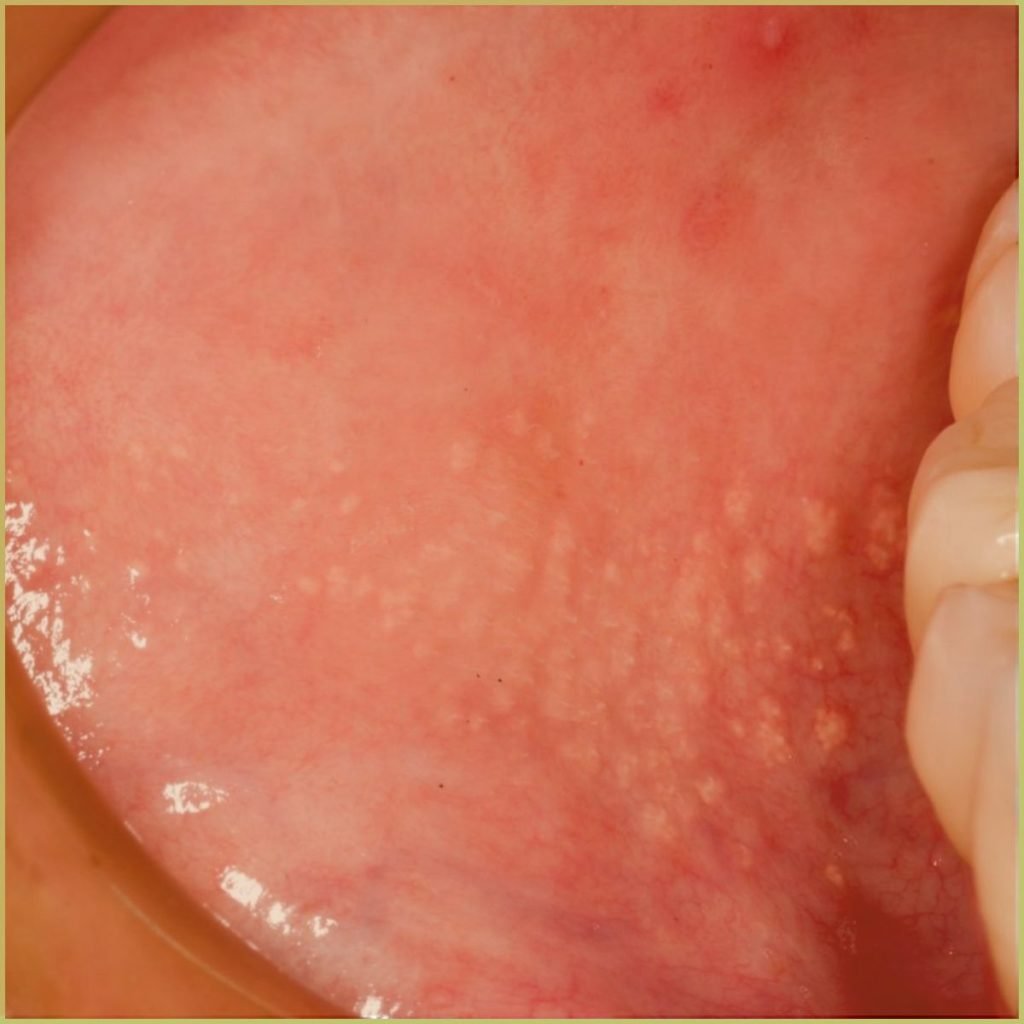

Fordyce’s Granules are painless small pimple-like structures caused by the presence of ectopic sebaceous glands within the oral mucosa and vermilion portion of the lips. The common clinical presentation includes:

- Bilateral areas scattered with yellowish-to-pink maculopapular granules.

- Usually located on the buccal mucosa, but may also be found on the vermilion of lips.

- Spots ranging from 1 to 5 millimeters in diameter.

- Appearance as solitary lesions or in clusters, often numbering between 50 to 100 spots.

- More pronounced visibility when the skin is stretched

- Asymptomatic nature, causing no pain, itching, or discomfort.

Diagnosis is usually based on the lesion history and clinical presentation alone. If a biopsy is indicated, microscopic findings may include:

- Normal sebaceous glands.

- Lack of hair follicles.

Your differential diagnosis should include:

- Sexually transmitted infections (STIs) such as genital warts or molluscum contagiosum.

- Sebaceous hyperplasia, involving the enlargement of sebaceous glands on the face.

- Epidermoid cysts, which are benign cysts filled with keratin.

- Genital lichen planus, an inflammatory condition causing flat-topped, violaceous papules.

- Candidiasis.

No treatment is required and the lesions are simply monitored. The prognosis for Fordyce’s granules is excellent. They are benign and asymptomatic, posing no health risks or requiring medical treatment. However, some individuals may seek treatment for cosmetic reasons.